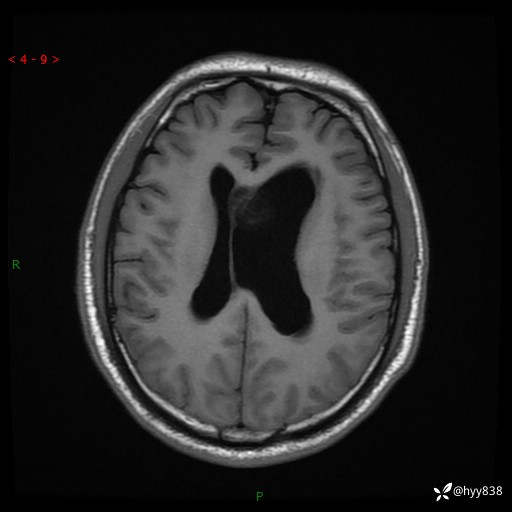

颅脑MRI平扫+增强